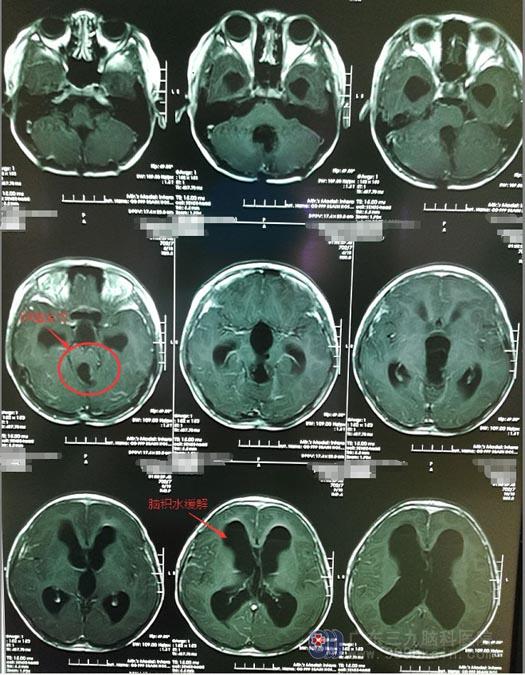

暂时解除危险后,需要继续为小茵行“中脑复发胚胎发育不良性神经上皮肿瘤切除”。手术医生告知小茵的父母,肿瘤位于中脑导水管,是脑脊液流动比较狭窄的部位,容易造成脑积水;中脑有后组颅神经通过,受损容易出现声音嘶哑,吞咽苦难等;这个部位也是人的意识中枢,如果损伤,容易造成长期昏迷;加上肿瘤的部位深,手术时很难操作,所以风险非常大。

由医院副院长、神经外五科主任鲁明主刀采取右额纵裂-胼胝体-穹窿间入路,见肿瘤位于中脑导水管周围,沿后下方生长,侵犯中脑,镜下分块切除,出血不多。手术非常成功。术前小茵就有双眼眼睑闭合不全,嘴角歪斜,眼球运动障碍的症状,术后未出现声音嘶哑,饮水呛咳,吞咽苦难等新的后组颅神经症状。